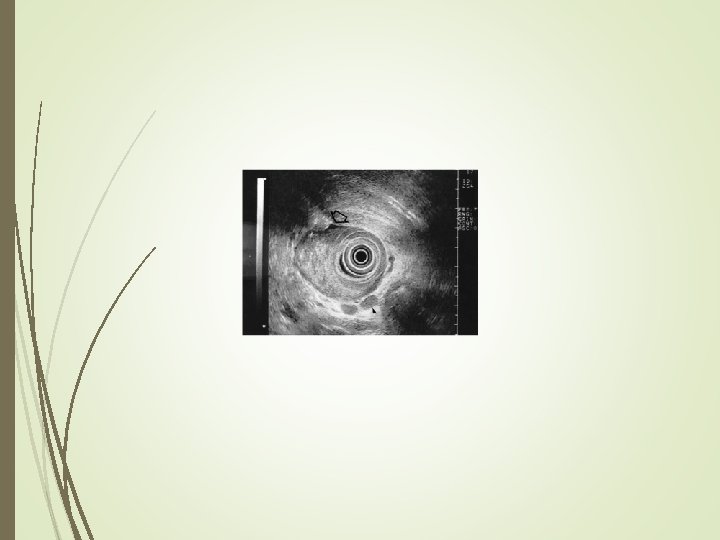

Diagnosis Endoscopic Ultrasound (EUS) is a newer modality that is being used in some center to help stage the tumor. Extent of wall invasion and lymph node involvement can be assessed. Overall accuracy is 75%. Poor for T 2 tumors (38%) Better for T 1 (80%) and T 3 (90%) Remains operator dependent.